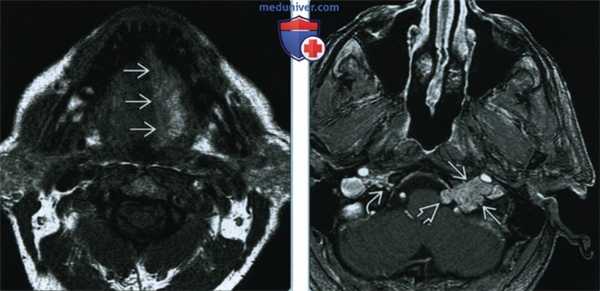

(Слева) МРТ Т1ВИ. Хроническая атрофия языка с выраженным повышением сигнала от левой его половины, которое характерно для жировой атрофии. Причиной паралича являлась параганглиома яремного отверстия (не показана).

(Справа) КТ с КУ, аксиальная проекция. Жировая атрофия вследствие хронической денервации левой половины языка. Правая половина языка выглядит крупнее левой, ее можно принять за опухоль. Как оказалось, причиной денервации является деструктивная костная опухоль на уровне подъязычного канала.

(Слева) На аксиальной МРТ (Т1 ВИ) определяются признаки хронической денервации языка с выраженным повышением интенсивности сигнала в его левой половине, сопоставимые с замещением жировой тканью. Подъязычная денервация может быть обусловлена параганглиомой яремного отверстия (не визуализируется).

(Справа) На аксиальной КТ с КУ определяется жировая атрофия вследствие хронической денервации левою подъязычного нерва. Правая половина языка выглядит больше, чем левая и может быть ошибочно принята за опухоль. Причиной денервации стала деструкция кости в области подъязычного канала.